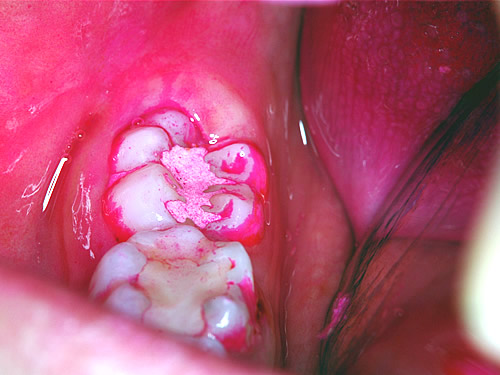

(図3)しかし、実験群の歯の表面には歯垢が付着していますが、セメントの上には見られません。(図4)4日後では、セメントの上にも付着が始まりました。このことからHY剤配合セメントには、歯垢の付着を抑制する効果があることがわかりました。(図5)タンニンの“抗菌作用”・“抗酸化作用”は、ヒトの口の健康にも影響をおよぼしていたのです。

図5